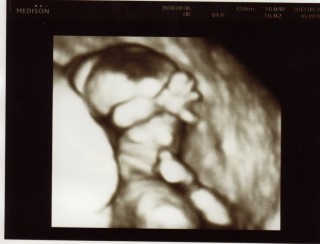

横向きの4Dです。下の子のときには4Dはありせんでしたので、はじめてみた4D、白黒とは違いすごく手や足がわかりやすかったです。